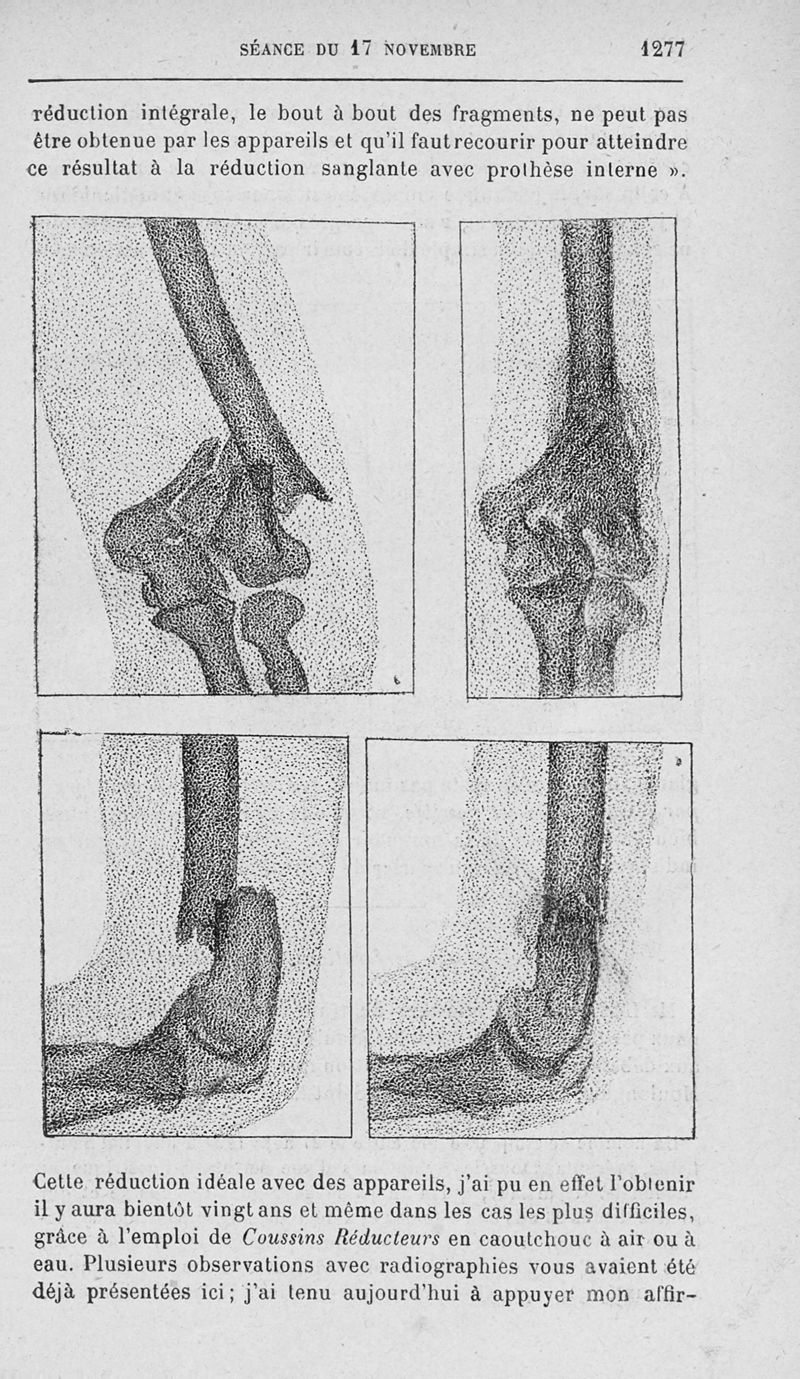

Bulletins et mémoires de la société de chirurgie de Paris

Tome XLVI, 1920. - Paris : Masson, 1920.